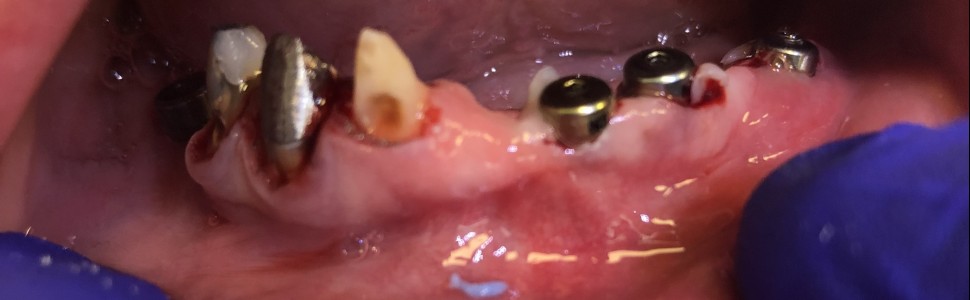

W artykule przedstawiono przypadek pacjentki, która utraciła zęby na skutek zapalenia przyzębia, w wyniku czego nastąpił zanik wyrostka zębodołowego szczęki i żuchwy oraz utrata tkanek miękkich. Zastosowano leczenie implantologiczne bez wcześniejszej odbudowy tkanki kostnej, umożliwiając wykonanie stałego uzupełnienia protetycznego na wszczepach zębowych. Etapy zabiegu zilustrowano zdjęciami. W wyniku takiego postępowania zostałosiągnięty sukces leczniczy, czynnościowy oraz estetyczny.

The article presents the case of a patient who lost her teeth as a result of periodontitis, which caused an atrophy of the alveolar process and loss of soft tissues. Oral implantological treatment was used without any previous bone tissue reconstruction enabling permanent prosthetic restoration on implants. The stages of the procedure were illustrated with photographs. As a result of this kind of proceedings, healing, functional and aesthetic success has been achieved.